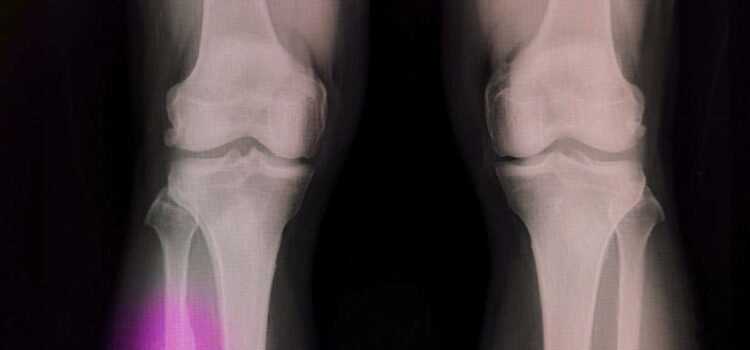

Broken bones often need a material to fill the voidSopone Nawoot/Alamy With slight modifications, hot glue guns commonly used in arts and crafts can repair damaged bones quickly and cheaply, researchers say. Bones can repair themselves after small injuries, but...